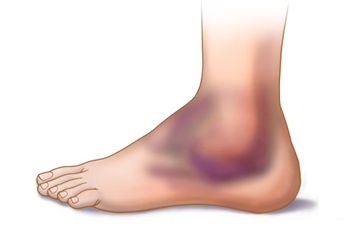

A história do paciente e o relato do trauma são importantes para a avaliação médica inicial e podem indicar a suspeita de uma fratura. A incapacidade de apoiar o pé no chão, dor á palpação óssea do tornozelo, inchaço importante e hematomas, são sinais clínicos normalmente presentes nas fraturas do tornozelo.